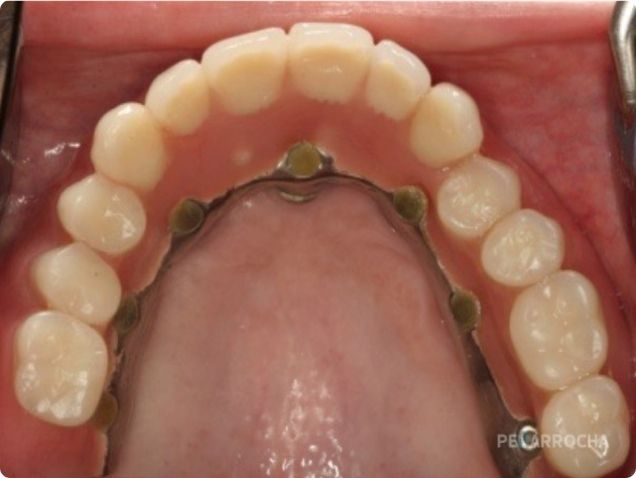

4. Si hay estabilidad suficiente, se puede colocar una prótesis provisional inmediata.

5. Tras la osteointegración, se coloca la prótesis definitiva.

• Reduce el tiempo de tratamiento y facilita la carga inmediata.

Puede combinarse con implantes palatinizados, cigomáticos o pterigoideos.